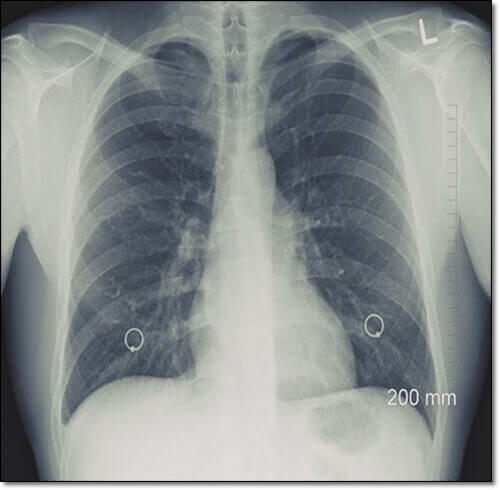

기관지 확장증을 검진하기 위해서는, CT나 X-ray 검사, 폐 기능 검사 등 다양한 검사를 통해 진단하게 됩니다. 또한, 기관지는 한번 손상되면 원래대로 돌아갈 수 없으므로 회복을 복적으로 하는 치료보다는, 증상의 악화를 방지하고 합병증을 예방하기 위한 약물과 외과적 치료를 시행하는 것으로 알려져 있습니다. 치료 약은 주로 항생제나 기관지 확장제, 점액 용해제 등을 사용하게 됩니다.